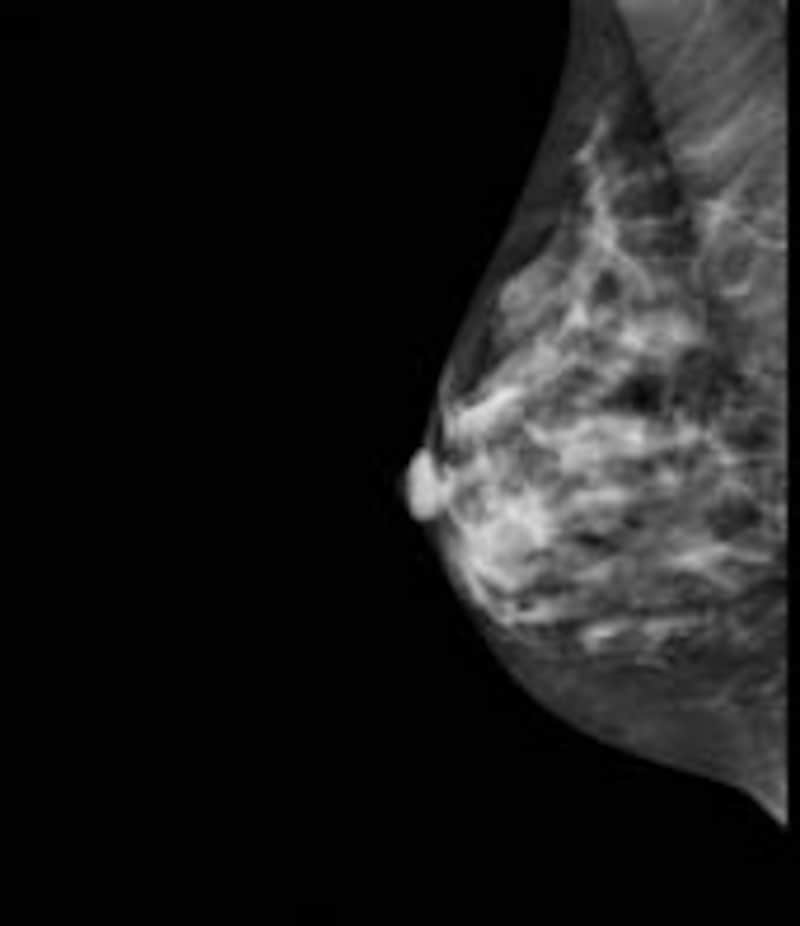

マンモグラフィー画像

| マンモグラフィーで見た乳房 |